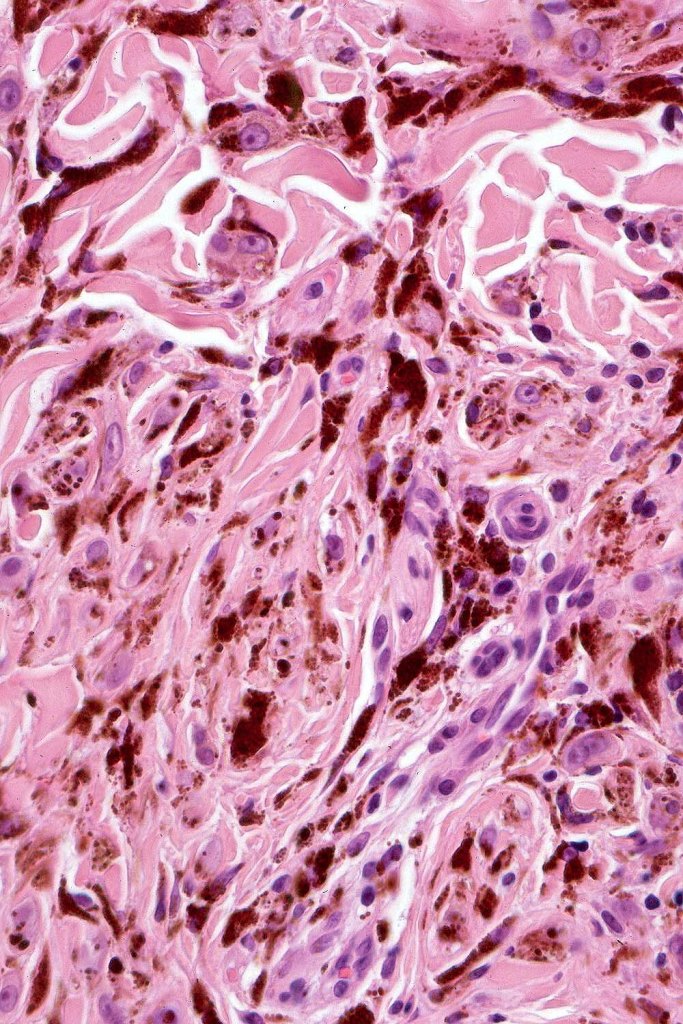

Combined common melanocytic nevus & BAP1-inactivated melanocytoma